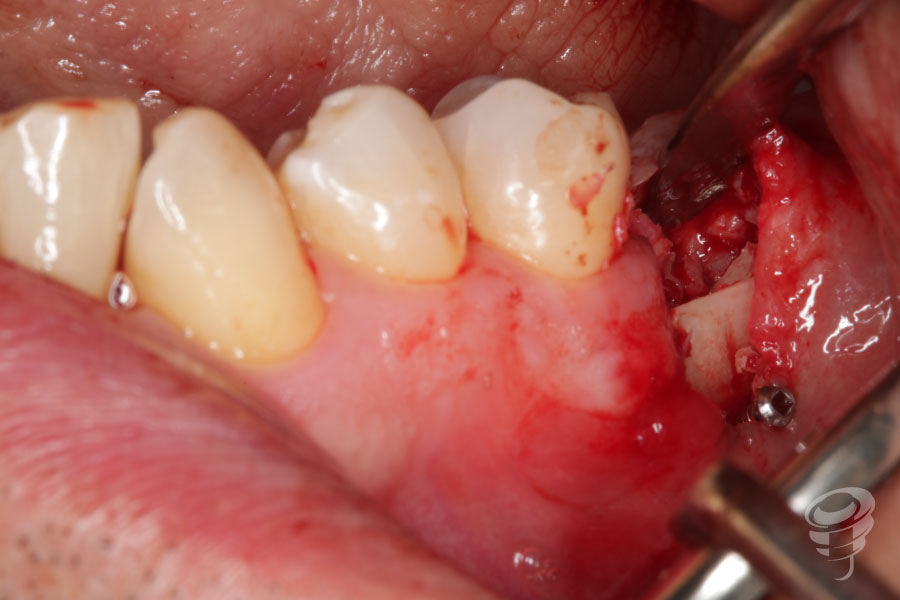

Cirugía de colocación de 2 implantes en posiciones 36 y 37. Se retiran también los tornillos de fijación de las láminas óseas y se realiza una radiografía periapical de control postoperatorio.

Figura 12 (A, B, C, D, E y F)